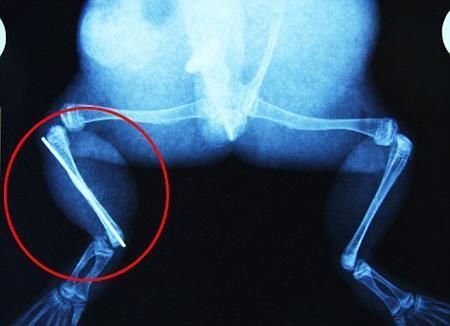

環(huán)球網(wǎng)4月2日?qǐng)?bào)道 據(jù)《每日郵報(bào)》報(bào)道,上個(gè)月,南非大牛蛙布魯萊的右小腿被鄰居家的一只狗咬到,導(dǎo)致粉碎性骨折,現(xiàn)在經(jīng)過2個(gè)小時(shí)的手術(shù),它的斷腿已經(jīng)被接上,它也因此成為有史以來第一只通過外科手術(shù)用鋼針接上斷腿的青蛙。

野生生物專家安妮經(jīng)常為學(xué)校寫教材,她認(rèn)為這是人類第一次通過手術(shù)給一只青蛙接斷腿。在手術(shù)開始階段,獸醫(yī)把少量給狗用的麻醉藥注入到這只青蛙體內(nèi),讓它失去知覺。然后他在布魯萊的斷腿上切開一個(gè)小口,把一根小鋼針植入腿里。最后獸醫(yī)給它縫了9針,把切口縫合在一起。僅僅幾周后,布魯萊就能在安妮家附近活動(dòng)了。這只青蛙大約已有25歲,主要以嚙齒動(dòng)物、蛇和其他青蛙為食。布魯萊所屬的牛蛙種群正在不斷減小,目前只能在非洲南部的濕地里才能看到這種青蛙。

安妮有2個(gè)孩子,她已經(jīng)從事20多年兩棲動(dòng)物保護(hù)工作。她認(rèn)為鄰居家的狗狗在把布魯萊從地下刨出來的時(shí)候,它正在地下冬眠、她說:“世界上只有這個(gè)地區(qū)能看到這種牛蛙,這種青蛙現(xiàn)在變得越來越稀少。因?yàn)槲覐氖乱吧锉Wo(hù)工作,因此認(rèn)識(shí)很多兩棲動(dòng)物專家,但是以前他們誰也沒見過這種事情?吹讲剪斎R越來越健康我非常開心,F(xiàn)在還需要一段時(shí)間,它的金屬腿和它的骨骼才能融為一體,那時(shí)布魯萊會(huì)跟以前一樣健康。我們認(rèn)為這個(gè)過程需要幾周時(shí)間,但是一旦它完全康復(fù),我希望把它放歸大自然,讓它重新回到它最鐘愛的濕地里!